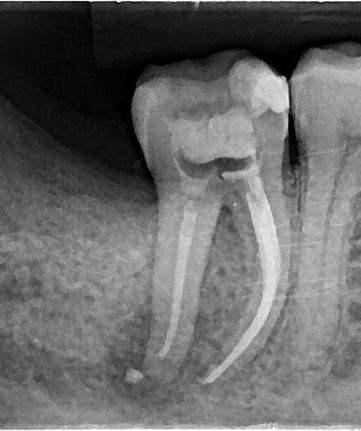

casos realizados

Especialista em Endodontia pelo Instituto Orbis Curitiba - PR em 2023;

Atuou em diversas clínicas e consultórios, hoje estando mais focada dentro da sua especialidade, trabalhando com o endodelivery.